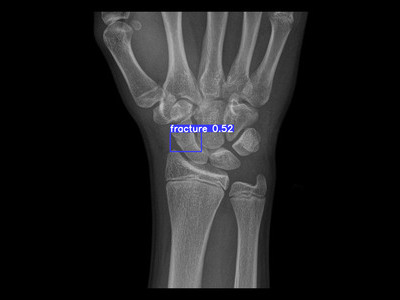

Detecção de fratura do escafóide em Raio X

Fratura do escafóide